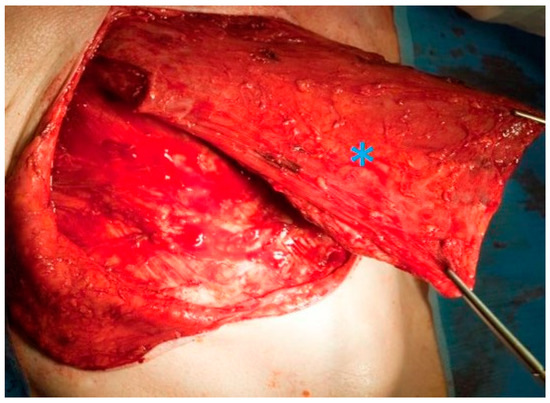

Figure 4.

Raising a pectoralis major pedicle flap (blue asterisk) to prevent wound healing problems such as fistula formation in a salvage laryngectomy.